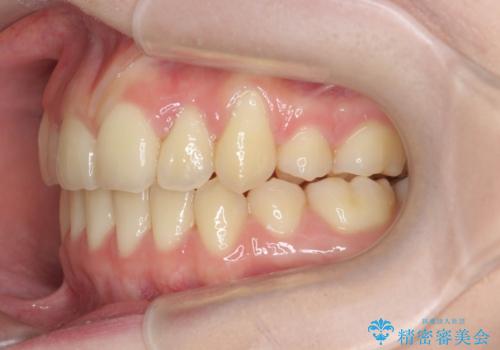

歯並びのせいで歯ブラシがしづらい マルチブラケットを用いた抜歯矯正

- 歯並びのがたつきにより歯ブラシがしづらく、今後虫歯になってしまう不安から、矯正治療を希望されて来院されました。

歯を並べるにはスペースが不足しているため、小臼歯の抜歯を4本行うマルチブラケット矯正による治療を計画します。

治療後は非常に歯ブラシがしやすくなったと、治療結果に満足いただくことができました。